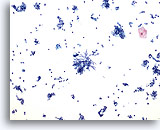

Actinomycetos

Los Actinomycetos pueden estar presentes en el esputo. Observar las bacterias filamentosas. 60x

Actinomycetos

Los Actinomycetos pueden estar presentes en el esputo. Observar las bacterias filamentosas.

60x